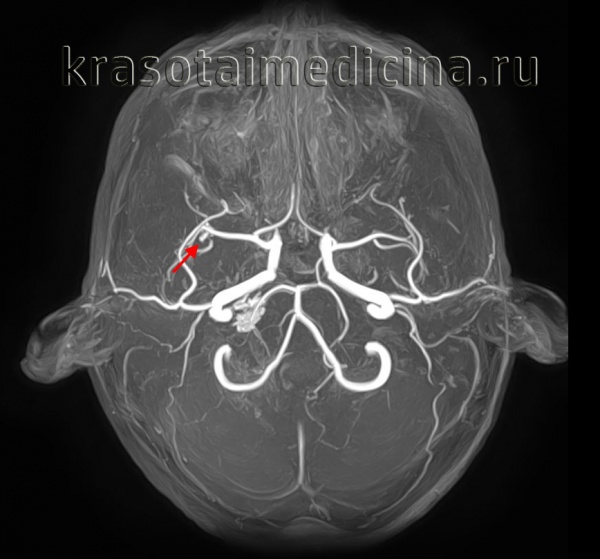

Добавлено: 03.03.2023, 04:20 Источник: Аневризма, мешковидное выпячивание стенки артерии или, очень редко, вены, которое возникает в месте ее перерастяжения, истончения и как следствие ослабления. ![]() Причиной аневризмы могут быть заболевания, приводящие к слабости сосудистых стенок, такие, как артериосклероз, артериальная гипертония, сифилис (на поздней стадии). При заболевании, называемом медиальным некрозом, возникает расслаивающая аневризма, т.е. расслоение (по ходу сосуда) стенки одной из артерий, обычно аорты. Расслоение возникает в результате того, что через небольшой надрыв, образовавшийся во внутренней оболочке аорты, кровь попадает в средний слой ее стенки. Отделяя один слой стенки от другого, она может прокладывать в ней дополнительный канал. У части больных через новый разрыв внутренней оболочки аорты кровь возвращается в основной канал, но иногда процесс расслоения продолжается вплоть до артерий ног. Таким образом, аневризма обычно вызывает не локальное расширение сосуда, а увеличение его диаметра на значительном протяжении, иногда по всей длине. Причины аневризмыскопление холестерина на стенках сосудов головного мозга заболевания сердечно-сосудистой системы вредные привычки — алкоголизм, табакокурение, пристрастие к наркотикам опухолевые новообразования инфекционные заболевания — например, сифилис травмы сердечно-сосудистой системы и головного мозга генетические отклонения — к примеру, поликистоз почек приобретенные заболевания — например, атеросклероз инфаркт миокарда, провоцирующий аневризму сердца Виды аневризмы Мешотчатая. Это — самая распространённая форма болезни. Напоминает мешочек, заполненный кровью. Прикрепляется шейкой или основой к артерии или местам отделения сосудов. Чаще всего локализуется у основания головного мозга. Боковая. Внешне походит на опухоль одной из стенок сосуда. Веретенообразная. Появляется из-за патологического расширения стенки сосуда. Аневризмы могут быть также связаны с травмой сосудов или образованием инфицированных тромбов (сгустков крови). Тромбы оседают чаще всего в более мелких сосудах, и их инфицирование, распространяясь на сосудистую стенку, приводит к формированию аневризмы. Классификация По своей форме аневризма сосудов головного мозга бывает мешотчатая и веретенообразная. Причем первые встречаются намного чаще, в соотношении примерно 50:1. В свою очередь мешотчатая форма может быть одно- или многокамерной. По локализации выделяют аневризму передней мозговой артерии, средней мозговой артерии, внутренней сонной артерии и вертебро-базилярной системы. В 13% случаях наблюдаются множественные аневризмы, располагающиеся на нескольких артериях. Существует также классификация по величине. Согласно ей выделяют аневризмы : - милиарные - размером до 3 мм - малые — до 10 мм - средние — 11-15 мм - большие — 16-25 мм - гигантские — более 25 мм. ![]() МР-ангиография сосудов головного мозга. Мешотчатая аневризма правой средней мозговой артерии. Аневризмы часто бывают бессимптомными и обнаруживаются случайно при ультразвуковом или рентгенологическом исследовании. Симптомы, как правило, возникают в случае сдавливания соседних структур. При разрыве аневризмы происходит кровоизлияние, которое приводит к тяжелому состоянию и нередко к смертельному исходу. Симптомы аневризмыЗаболевание часто никак себя не проявляет. Иногда появляются следующие симптомы: - снижение остроты зрения и нарушения движения глазных мышц - онемение мышц лица - мигрени и головные боли, которые могут сопровождаться потерей сознания - тошнота и рвота - ощутимая пульсация в животе - затруднение дыхания, кашель и боль при глотании - острая боль в животе, иногда отдающая в спину Методы диагностики Чтобы уточнить вид аневризмы и поставить диагноз, врач направляет пациента на дополнительные исследования: например, на допплерографию сосудов головного мозга или ангиографию. Наиболее эффективным методом диагностика является магнитно-резонансная томография (МРТ). К какому врачу обратиться Запишитесь на консультацию к кардиологу — он специализируется на заболеваниях сердечно-сосудистой системы. Врач поставит диагноз и назначит грамотное лечение. Лечение аневризм – хирургическое: пораженный сегмент сосуда вырезают и заменяют либо пластиковым протезом, либо участком кровеносного сосуда из другой части тела. Разорвавшаяся аневризма сосудов головного мозга является неотложным состоянием и требует консервативного лечения аналогичного лечению геморрагического инсульта. По показаниям проводят хирургическое лечение: удаление гематомы, ее эндоскопическую эвакуацию или стереотаксическую аспирацию. Если аневризма сосудов головного мозга сопровождается кровоизлиянием в желудочки производят вентрикулярное дренирование. Смотрите видео - АНЕВРИЗМА сосудов мозга: чем ОПАСНА и как ее обнаружить |